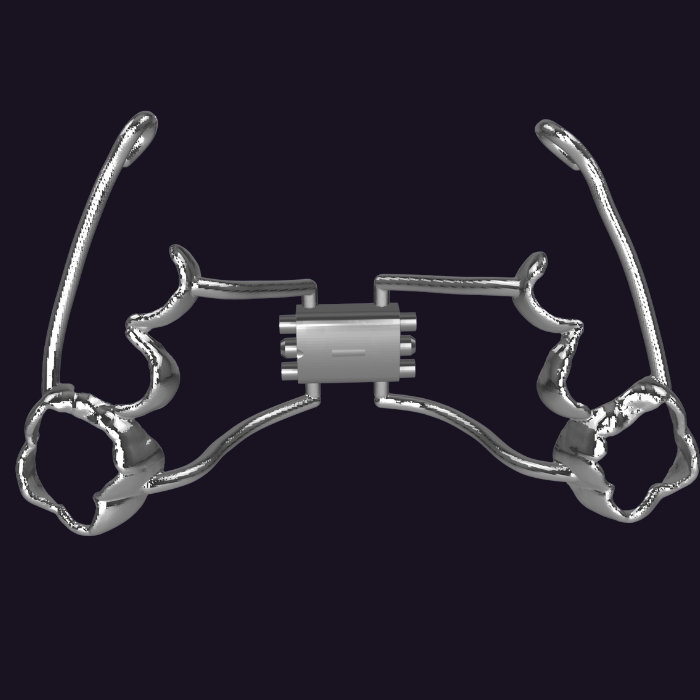

MARPE Aksesuarları

MARPE sistemleri için özel tasarlanmış aksesuarlar ve eklentiler. Ekspansiyon, intrüzyon, distalizasyon gibi ihtiyaç duyulan tüm eklentiler tek sistemde.

- Ekspansiyon eklentileri

- İntrüzyon ve distalizasyon modülleri

- Özel tasarım ve uyum garantisi

- Tak-çıkar yapmadan kol kesimleri ile uygulama